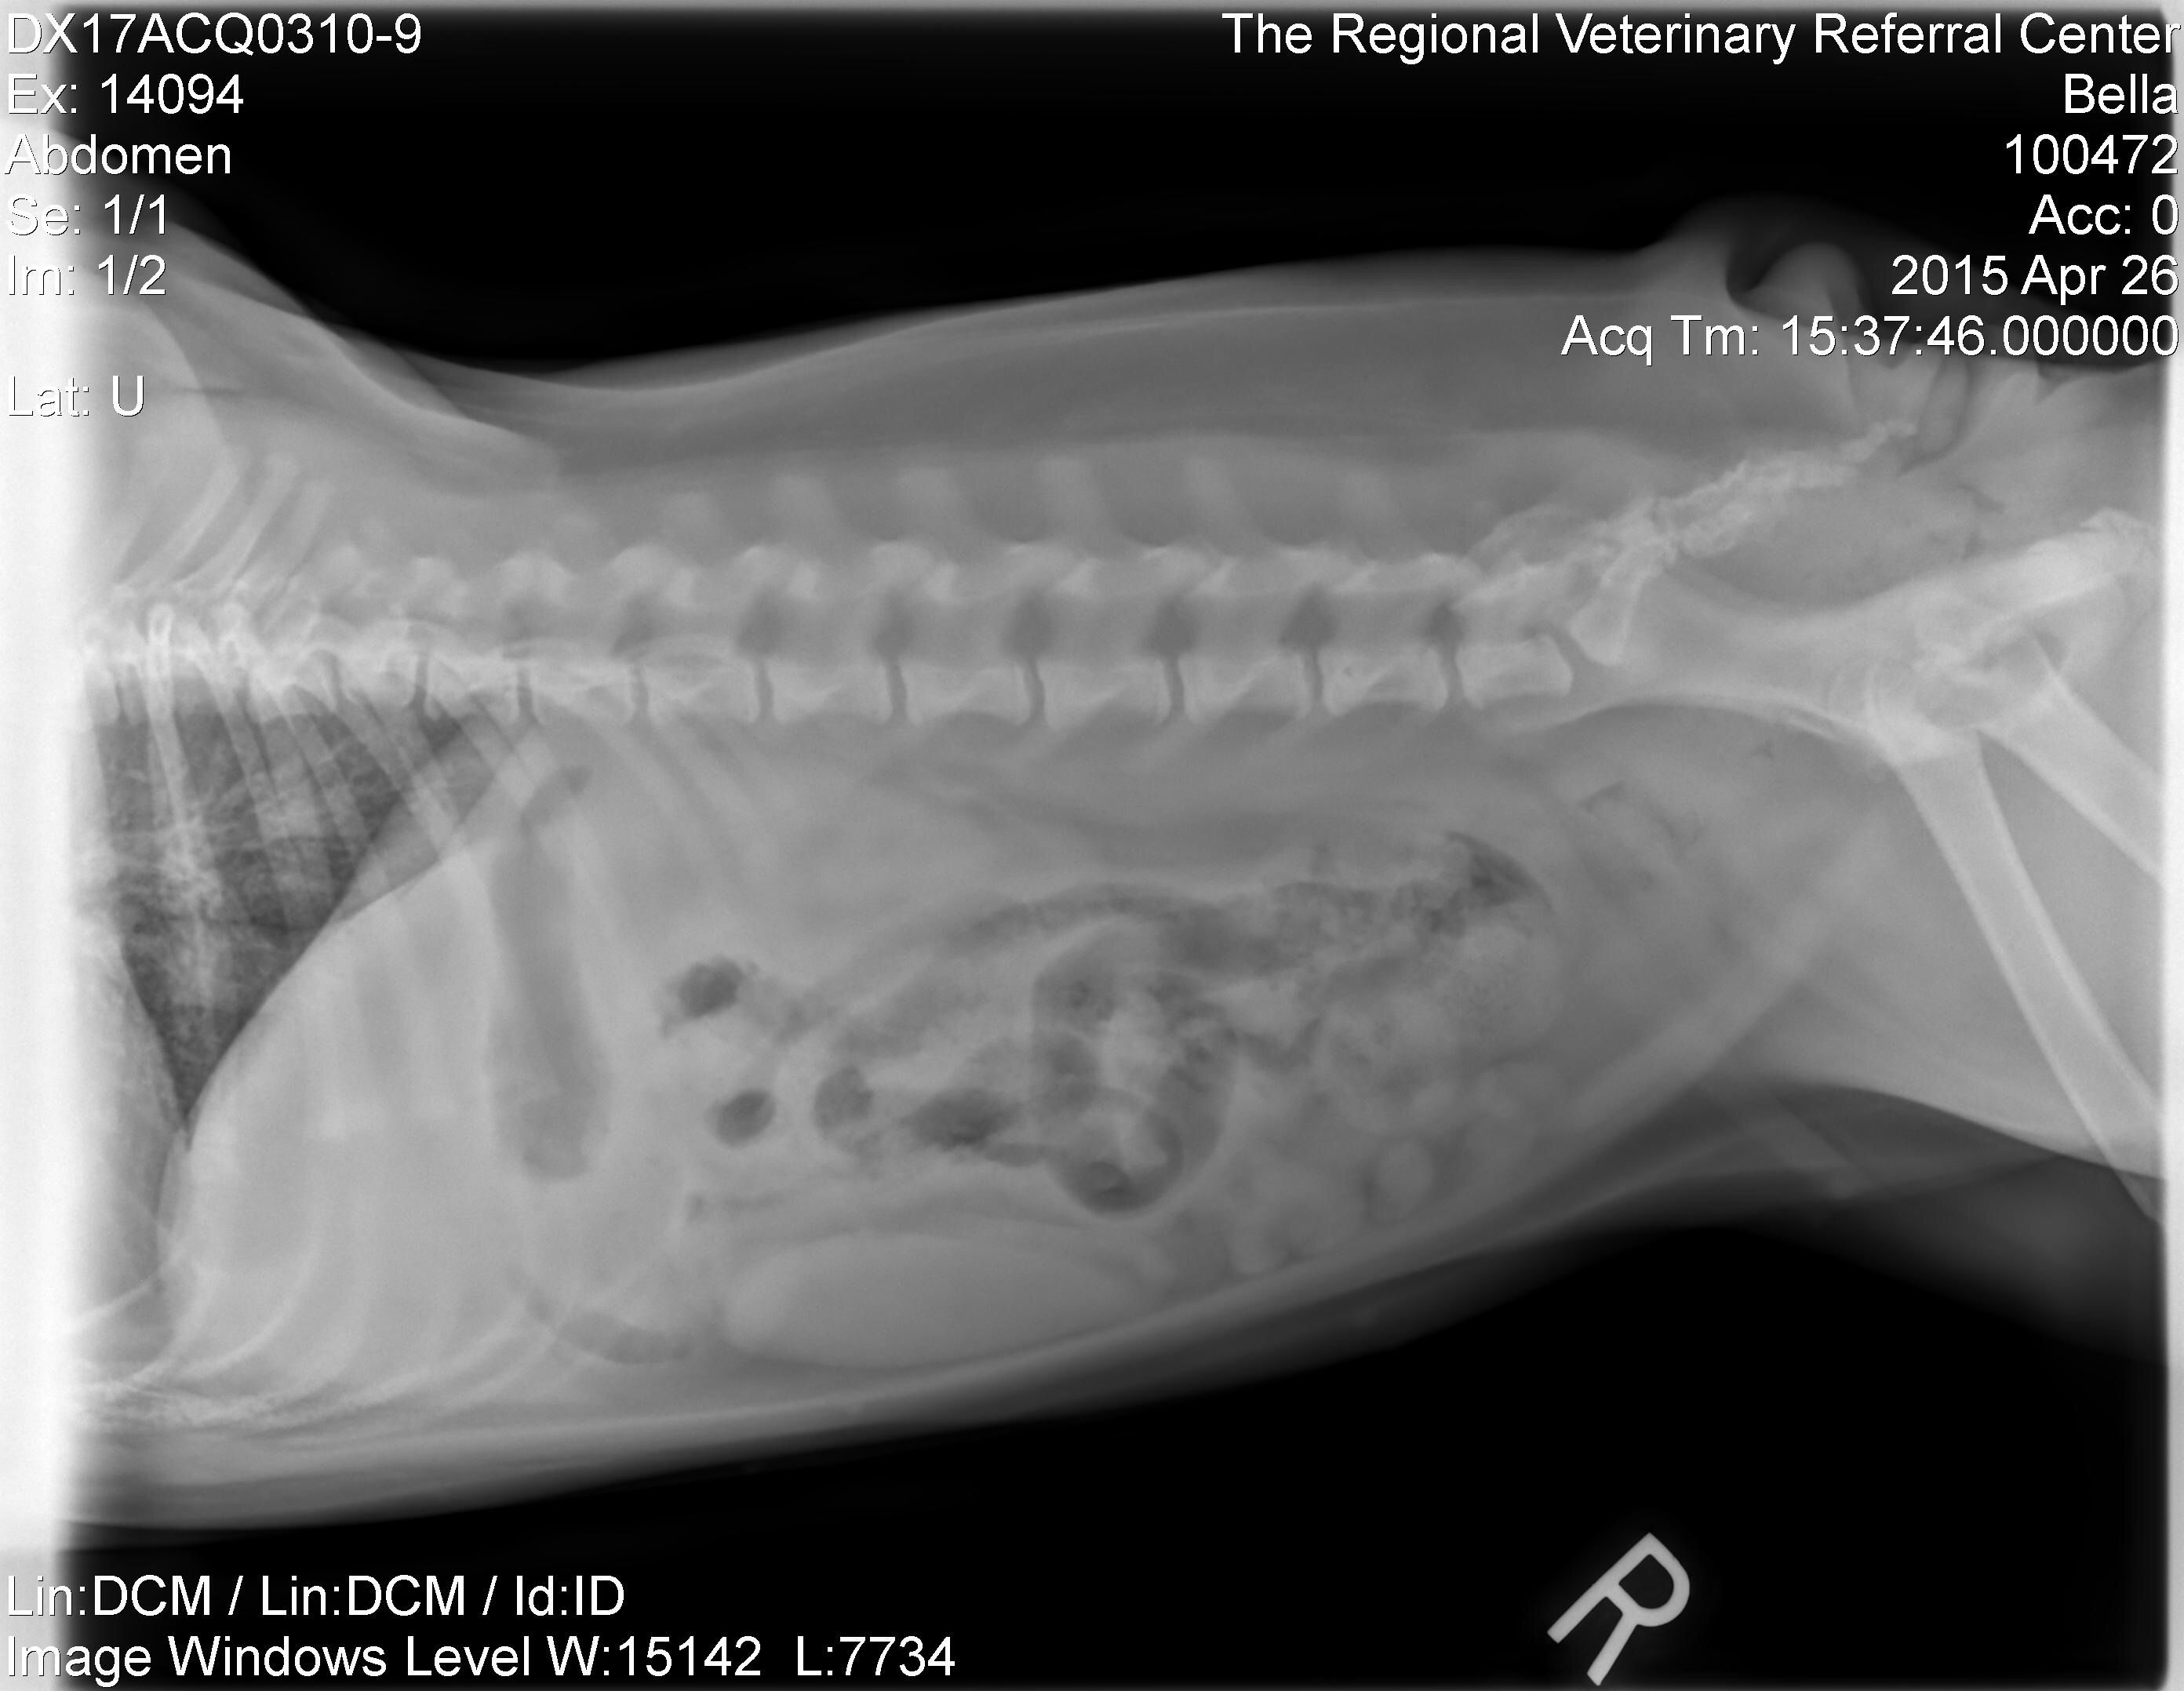

[MENTION=13133]TyTysmom[/MENTION] here are the xrays!

View attachment 86755View attachment 86756

The questionable item is a very faint sand dollar looking object in the lower right. It's identifyable only on the side picture, not on the back picture. What do you think??

Awesome!! What did they say it "could" be initially? I see it and it's near the intestines but not in them from what see ...